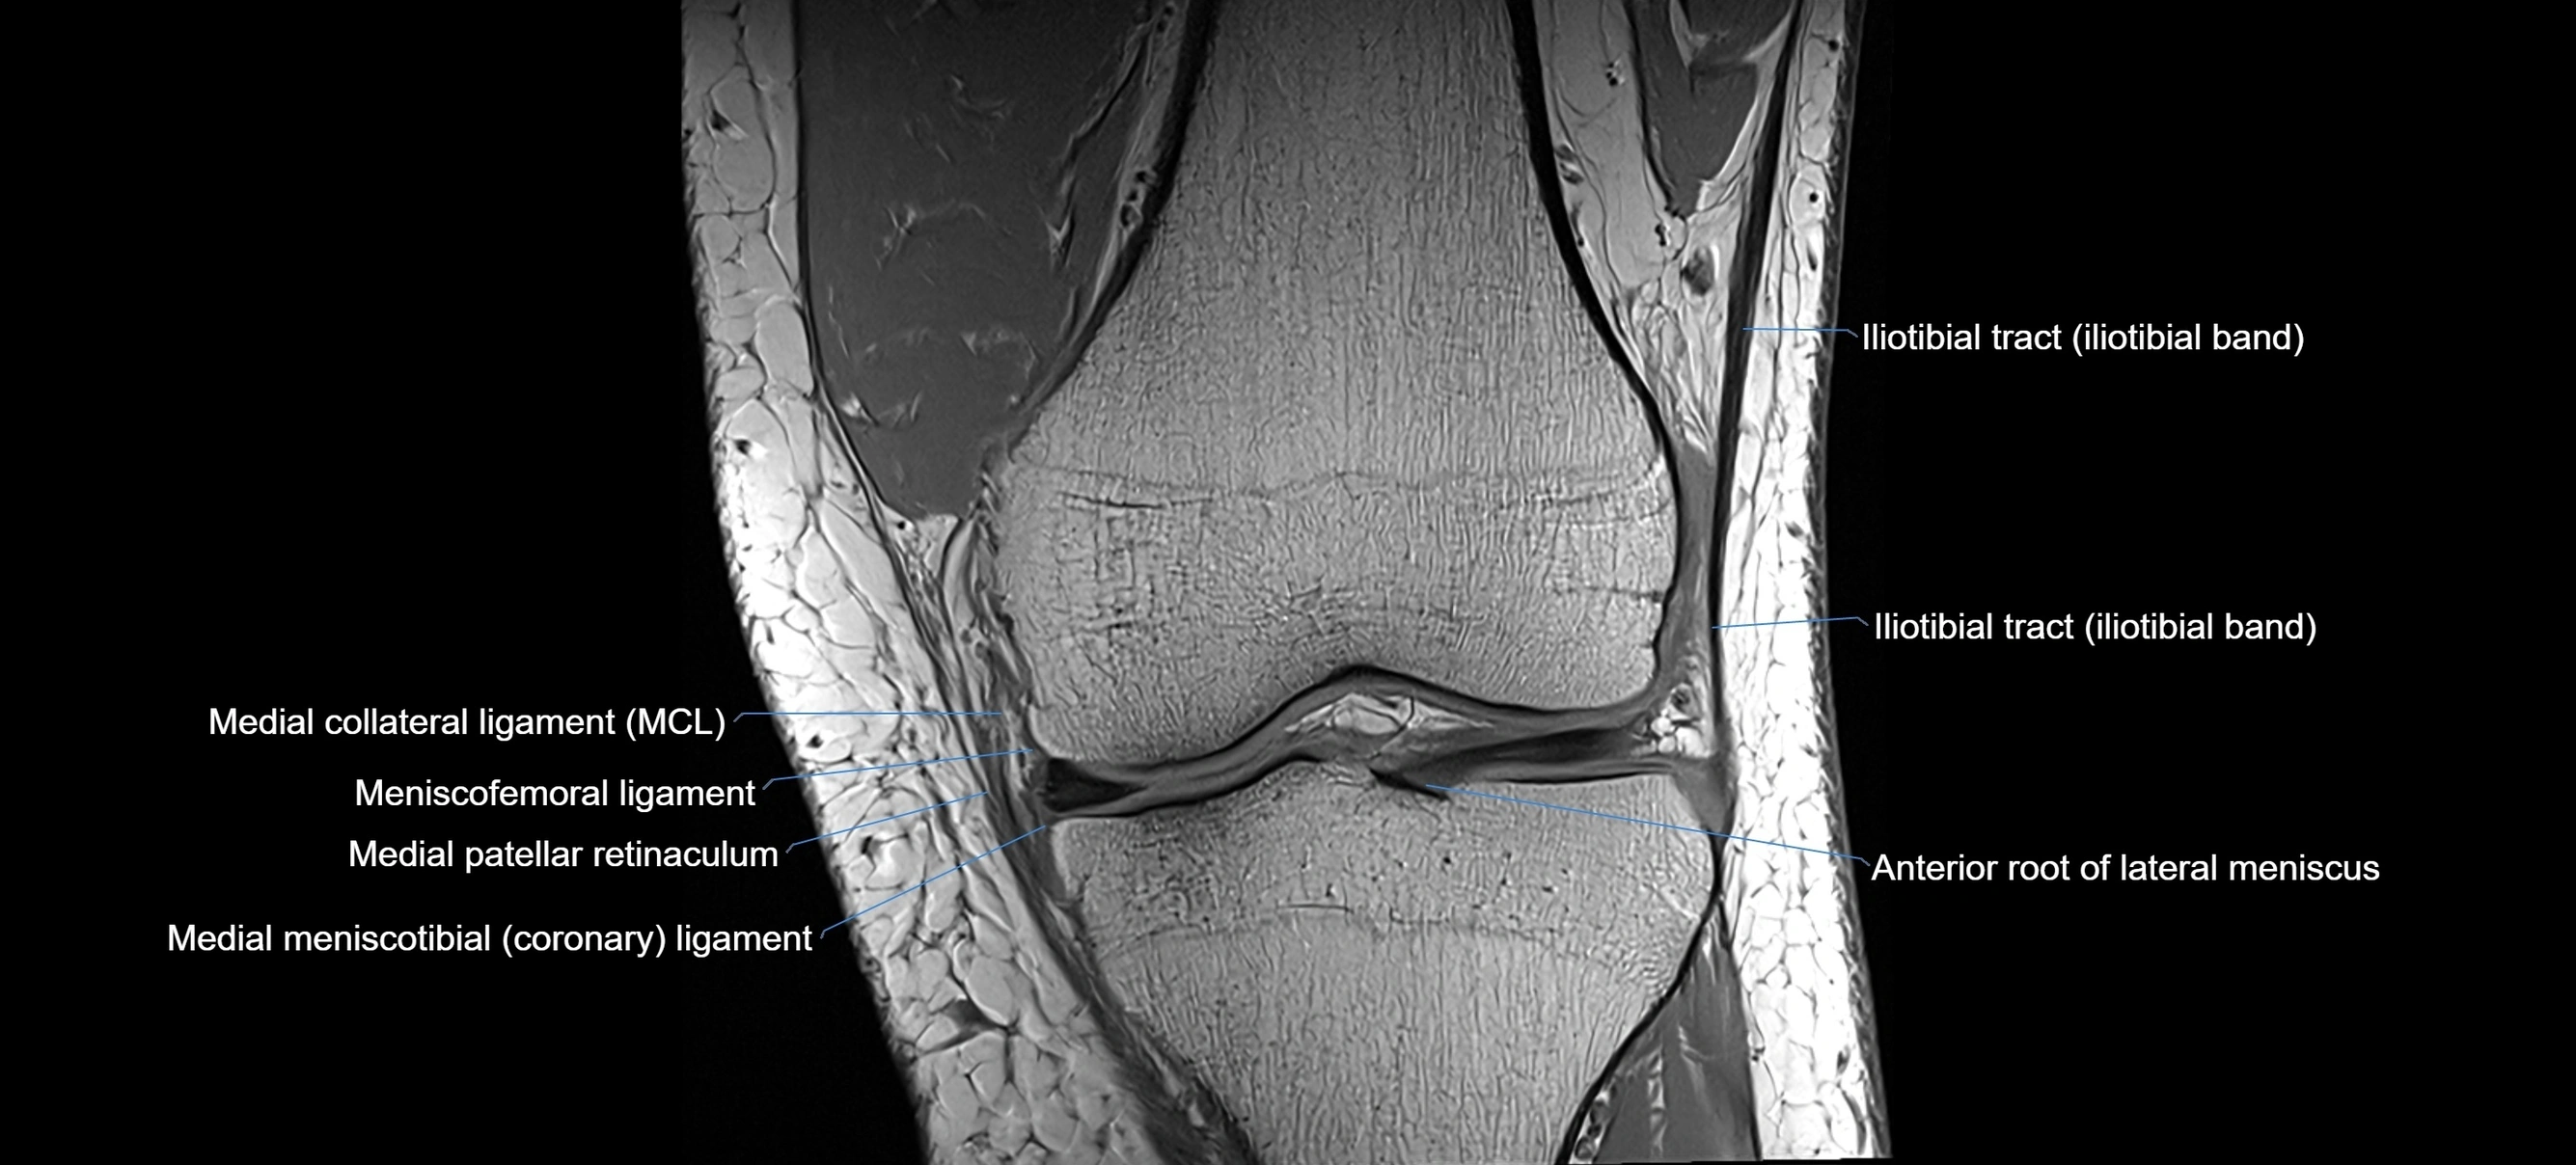

MRI Appearance

T1-weighted images:

• Normal ACL appears as a low-signal band-like structure crossing the intercondylar notch

• Surrounded by intermediate signal synovial fluid and fat planes

T2-weighted images:

• Normal ACL remains low signal

• Partial or complete tears appear as discontinuity, increased signal, or fiber laxity

MRI images

image